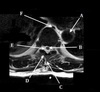

19

What is letter A?

A

SPINAL CORD

20

What is letter B?

LIGAMENTUM FLAVUM

21

What is letter C?

SPINOUS PROCESS

22

What is letter D?

CSF

23

What is letter E?

VERTEBRAL BODY

24

What is letter F?

STERNUM

25

What is letter H?

SUPRASTERNAL NOTCH